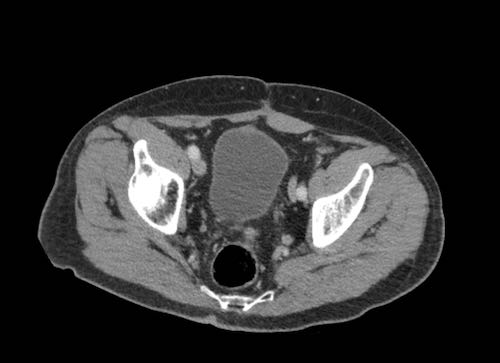

Ca lâm sàng 2

Cuộn qua các lát cắt.

Bạn có thể phát hiện tất cả các tổn thương cấy ghép phúc mạc không?